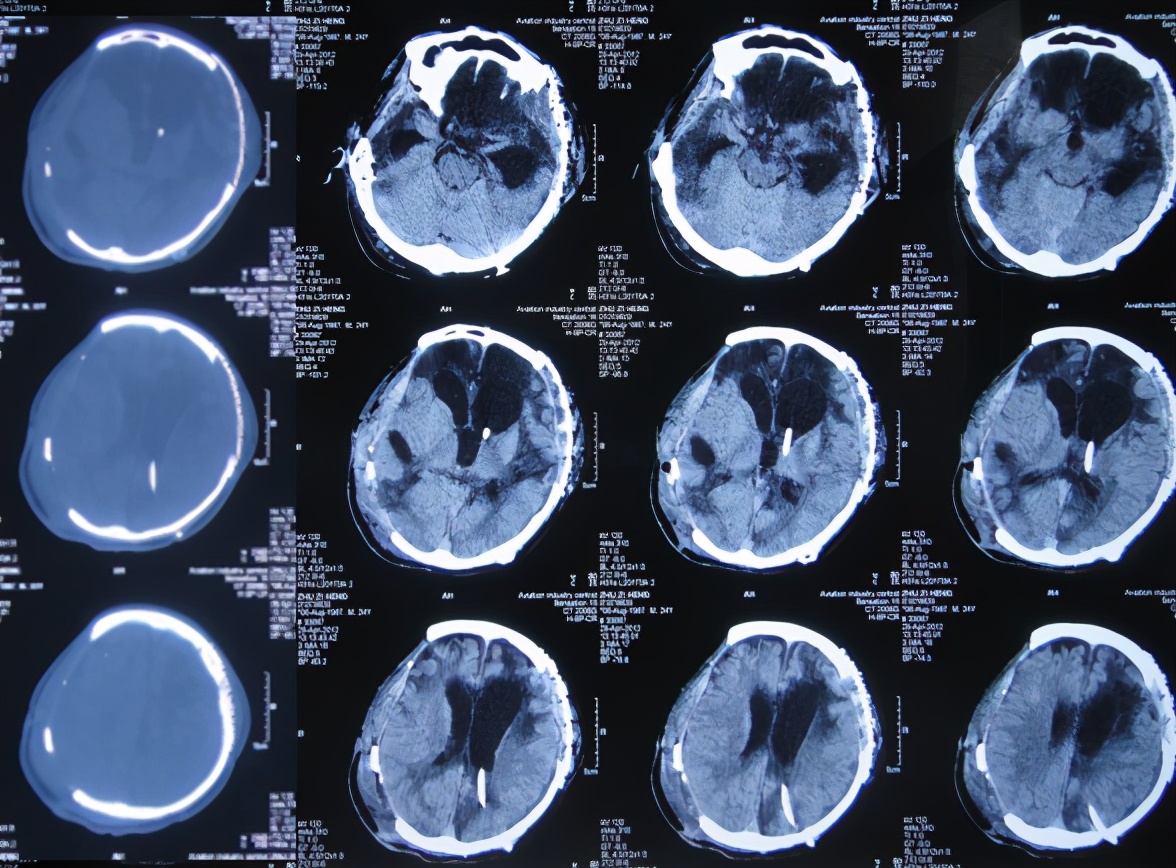

患者于2011年1月14日晚11点,意外发生车祸当即昏迷,120救护车将其送往第1家的安徽省合肥市的某三甲医院,查头颅CT:重度颅脑损伤,脑出血( 图-1 )。

图-1: 2011年1月15日头颅CT

当天急诊去骨瓣减压术;术后当天查头颅CT示双侧去骨瓣减压术后状态( 图-2 )。

图-2: 2011年1月15日术后头颅CT